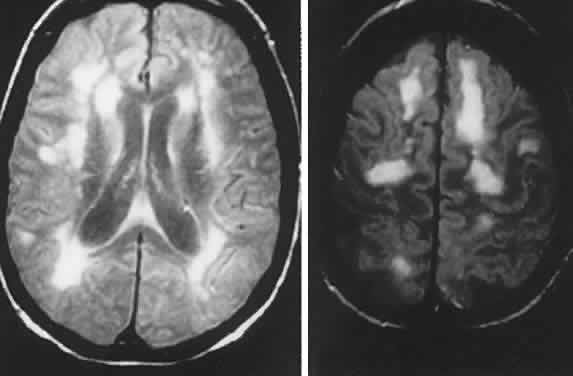

Other subsets of pigmentary retinopathies are due to mitochondrial DNA mutations and are associated with migraine, ataxia, dementia, and Leigh's disease17; the sporadic or maternally inherited MELAS syndrome of mitochondrial myopathy, encephalopathy, lactic acidosis, and stroke-like episodes, usually presents in the teens as cognitive regression, headaches, and cerebral lesions causing field defects.18–20 Even in family members, there is considerable variation of genotypic and phenotypic specificity in metabolic disorders mediated by mitochondrial DNA aberrations, including Kearns-Sayre progressive external ophthalmoplegia (see Volume 2, Chapter 12) and other conglomerations of pigmentary retinopathies. Further identification of gene point mutations will eventually provide a more precise classification.

The late infantile type (Bielschowsky-Jansky) is a fatal recessively inherited disorder with genomic defect localized to chromosome 13q22, thus delineating this disease as a separate entity.32 Presentation is with developmental arrest and seizures at 2 to 5 years of age, with motor and visual symptoms thereafter. There is massive tissue accumulation of lysosomal hydrophobic subunit-c protein of the mitochondrial adenosine triphosphate synthase. Ganglion cells are decreased in number, with thinning of the nerve fiber layer and optic atrophy. In addition, there is involvement of the outer segments with degeneration of the rods and cones and pigmentary clumping in the outer retinal layers. On MRI, hyperintense periventricular signals correlate with severe loss of myelin.33